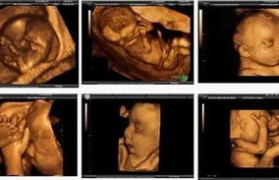

四维彩超检查作为孕期重要的产前筛查手段,其费用因地区、医院等级和检查项目不同而有所差异。本文将详细解...